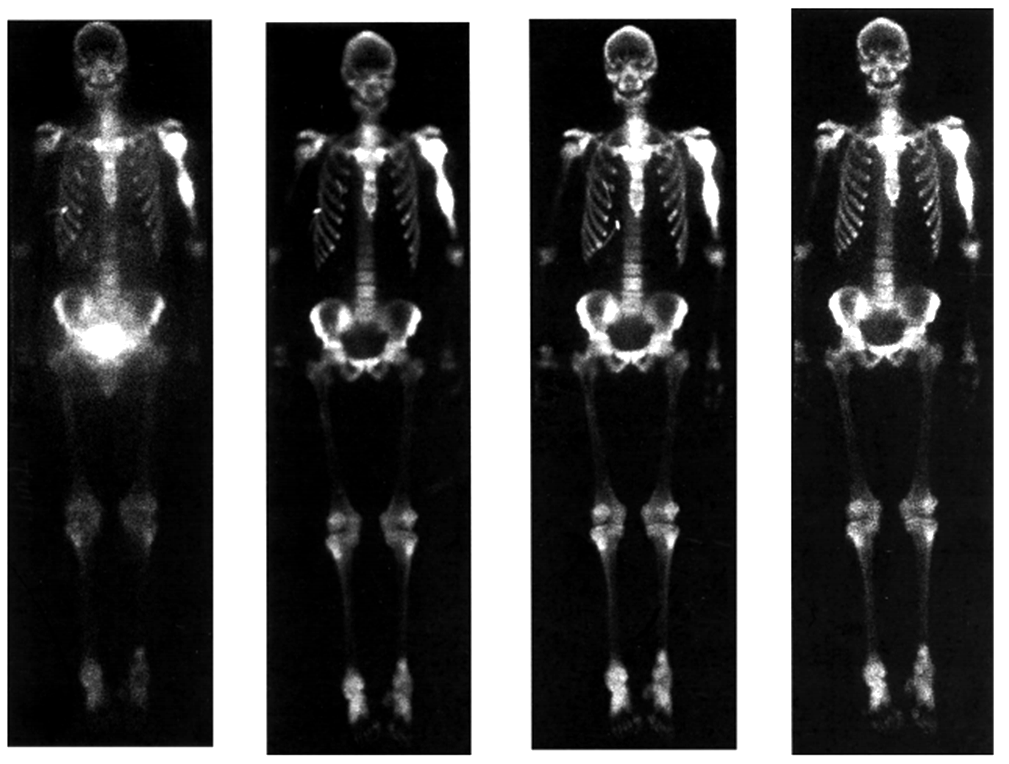

Pemberian injeksi 153Sm-EDTMP dilakukan secara intravena dengan dosis keradioaktifan sebesar 0,5-1,0 mCi/kg berat badan (rata-rata 50 mCi per satu kali penyuntikan). Kemudian dipindai dengan kamera gamma pada seluruh tubuh setelah 24 jam penyuntikan. Uji dilakukan kepada 10 orang pasien penderita kanker tulang metastasis, didapatkan hasil dengan rincian 4 orang merasakan rasa nyeri hilang secara keseluruhan, 5 orang merasakan rasa nyeri berkurang secara bertahap dan 1 orang tidak dapat dinilai efeknya karena tidak ada rasa sakit sebelum pengobatan. Selain itu juga terlihat pengurangan intensitas/jumlah metastasis pada 2 orang pasien dan toksisitas ringan pada 1 orang berupa menurunnya jumlah leukosit yang bersifat reversible/bolak-balik. Serta uji biodistribusi terhadap tikus, dapat dilihat pada tabel 1. aktivitas dari organ darah, hati, ginjal, otot, tulang, lambung dan usus halus dalam bentuk % dosis obat suntik per gram organ menunjukkan bahwa 153Sm-EDTMP terakumulasi lebih tinggi pada tulang dibandingkan organ lunak lainnya [2,7].